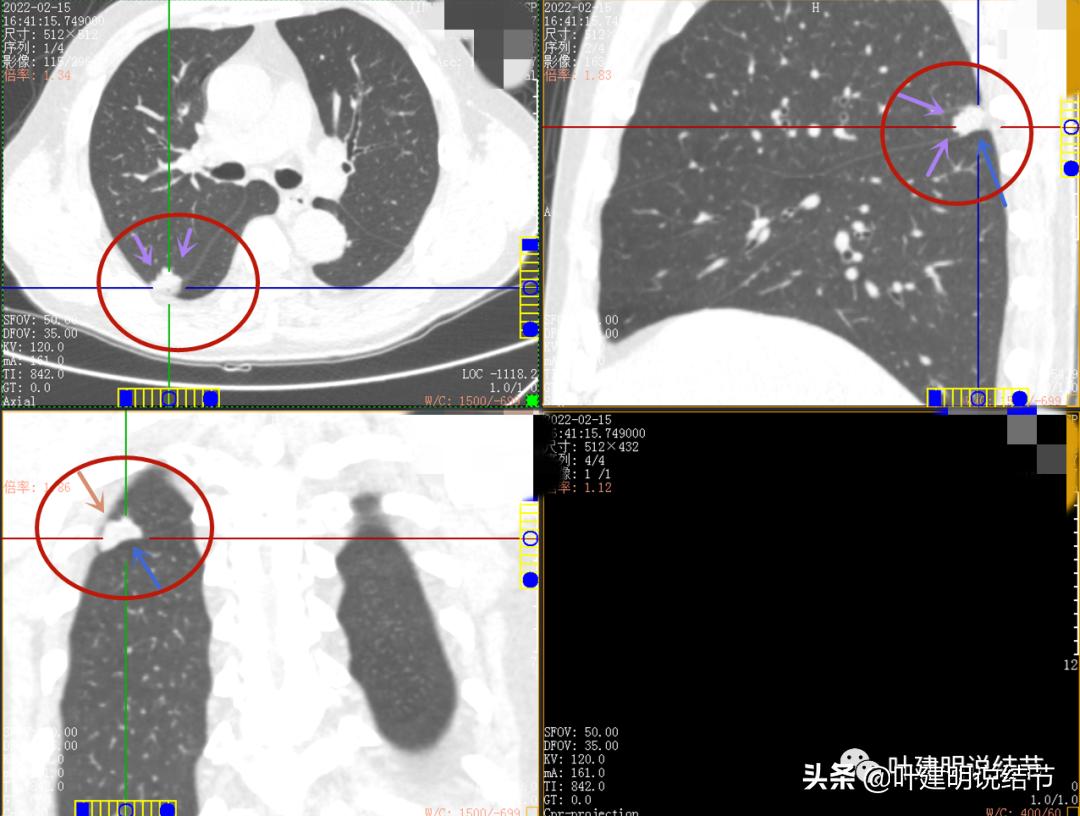

上图是轴位、冠状位与矢状位的图像

我们发现此病灶的影像特征有以下方面:

密度:实性且在纵隔窗上密度不均,强化不等;

边缘:边缘毛糙不平,有浅分叶,部分层面似有少许磨玻璃成分(薄薄的一层,不确切),对叶间胸膜有牵拉,但牵拉力并不强;

血管:有血管征,血管进入明显;

邻近:与胸壁紧贴,但两者之间有低密度的界限,表明一是没有水肿与糊墙征,二是肿瘤收缩力弱。

总体印象:右上叶此病灶基本可肯定为肺癌,不是贴壁为主型,也不似实体型(实体型的一般收缩力较强,毛刺征较为明显些),也不是很像腺泡型(腺泡型的密度不均,往往伴有贴壁成分,而且不是特别密实的那种),也不似粘液腺癌(粘液腺癌轮廓清,内部密度均匀)。大概会是乳头型或微乳头型,这两型我感觉影像上可能不一定看的出异常。